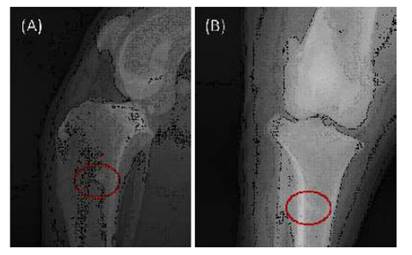

En la imagen radiográfica del posoperatorio inmediato del paciente canino (Figura 7) se visualiza una estructura radio-paca correspondiente al perfil completo del tornillo, donde no hay fractura o daño dentro de su estructura. En la imagen radiográfica del posoperatorio inmediato del paciente felino (Figura 8) se puede observar, de manera similar, que las imágenes radiopacas que corresponden a la tibia y al implante se visualiza completamente delimitado, sin fractura o daño dentro de su estructura. Así mismo, alrededor del implante se visualiza un halo radiolúcido, lo que diferencia el hueso del paciente con el implante insertado y corresponde a la inexistencia de osteointegración, la cual debe ocurrir en los meses posteriores a la cirugía.

Figura 7 Tornillo de hueso bovino liofilizado insertado en paciente canino sometido a cirugía de reparación extraarticular de ruptura de ligamento cruzado anterior. Radiografía tomada inmediatamente después de la cirugía, A) Vista frontal, B) Vista lateral